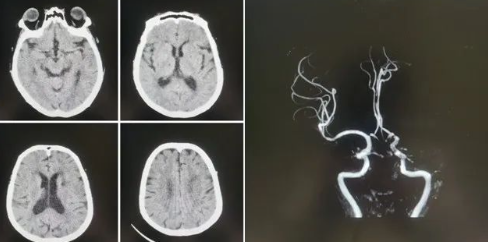

77歲的張阿姨(化名)家住公主嶺市劉房子街道,在活動中突發(fā)意識不清、言語不能,家屬在發(fā)病后1小時內(nèi)緊急將患者送至我院急診。急診科醫(yī)生第一時間查看病人,患者高齡,進(jìn)展性意識不清、言語不能,雙眼向左側(cè)凝視,壓眶疼痛刺激下左側(cè)肢體可抬起,右側(cè)肢體肌力0級,緊急啟動卒中救治綠色通道,立即進(jìn)行頭CT檢查,排除出血后,考慮急性缺血性腦卒中,因患者發(fā)病時間短,緊急聯(lián)系卒中中心團(tuán)隊(duì),國文醫(yī)院卒中中心丁金明主任第一時間聯(lián)系影像科進(jìn)行了頭部核磁血管檢查,確診為左側(cè)大腦中動脈急性閉塞。

緊急啟動導(dǎo)管室、麻醉科,在導(dǎo)管室、麻醉科人員的配合下在全麻下進(jìn)行了腦血管造影術(shù),造影顯示:III型弓,左側(cè)大腦中動脈M1段閉塞,余血管未見異常,立即進(jìn)行左側(cè)大腦中動脈閉塞取栓術(shù),因?yàn)榛颊逫II型弓,動脈硬化重,血管迂曲嚴(yán)重,在泥鰍導(dǎo)絲指引下,利用同軸技術(shù)(6F長鞘+5F多功能造影管)反復(fù)嘗試超選左側(cè)頸總動脈失敗。

在神經(jīng)介入團(tuán)隊(duì)丁金明主任、朱洪波副主任共同努力下,通過交換技術(shù)成功超遠(yuǎn)目標(biāo)血管,釋放取栓支架,通過取栓支架取出一團(tuán)塊狀血栓,成功開通左側(cè)大腦中動脈血流,挽救了患者的生命,術(shù)后頭CT檢查未見出血,轉(zhuǎn)入重癥監(jiān)護(hù)病房進(jìn)一步治療。